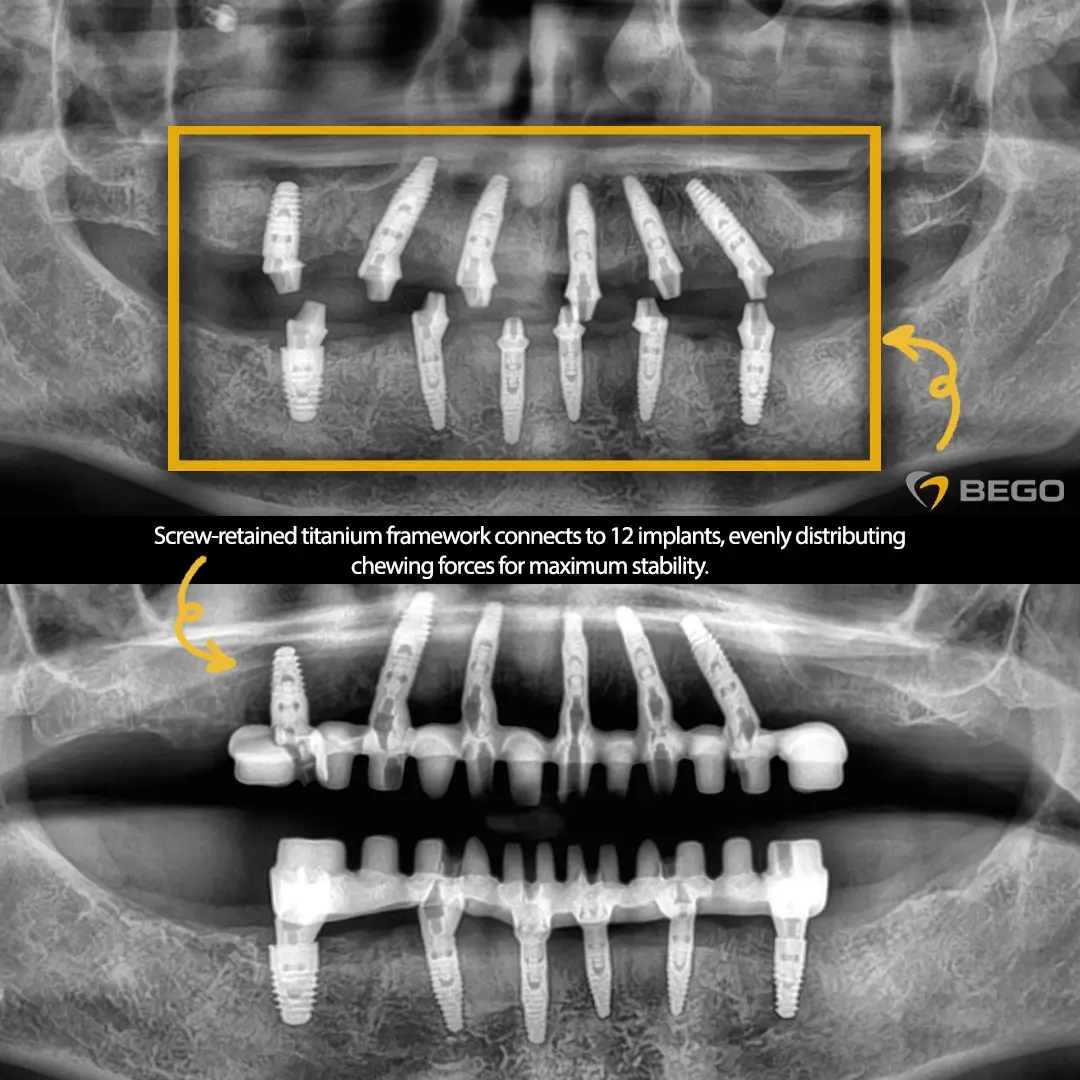

Surgical Phase: Twelve Implant Rehabilitation

Placing twelve dental implants in a single surgical session represents a significant technical challenge requiring surgical expertise, endurance, and meticulous planning. Most clinics divide full mouth rehabilitation into multiple surgical appointments due to increased surgical complexity and patient fatigue.

The surgical plan called for a total of twelve implants: six in the upper jaw and six in the lower jaw. This distribution provided adequate support for full arch prosthetic reconstruction while accounting for anatomical constraints and available bone volume.

Toronto Bridge Framework Advantage

The Toronto bridge represents a time tested approach to full arch implant rehabilitation. The Toronto bridge concept, originally developed by Professor Per-Ingvar Brånemark, has formed the foundation of modern full mouth rehabilitation.

In the patient’s treatment, it consisted of a screw retained titanium framework connecting directly to the twelve osseointegrated implants. This framework serves multiple critical functions in the overall restoration.

The titanium framework provides rigid stabilization that distributes occlusal forces evenly across all implants. Unlike individual crowns where each implant carries isolated loads, the Toronto framework ensures force sharing across the entire arch.